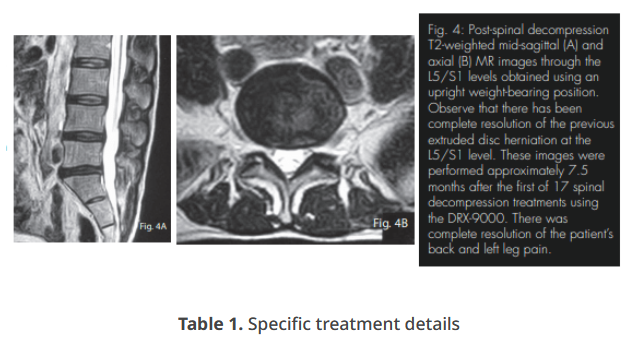

The seven treatments occurring at the prescribing doctor’s office are outlined in Table 1. The force applied was based on the patient’s weight of 125 lbs. Relief of radicular symptoms began following the first treatment, and eight weeks of follow-up care provided 100% reduction of all lower back and leg complaints. Approximately 7.5 months following the initial date of treatment, MRI re-evaluation of the patient’s lumbar spine was obtained. These scans were performed at the same imaging center and using the same standard imaging protocols for a neutral seated (weightbearing) position. The images were read by a medical radiologist. The scans through the L5/S1 level demonstrated mild decreased signal intensity within the disc consistent with desiccation and degenerative change, as well as a complete resolution of the previous paracentral extruded disc herniation. There is no longer evidence of thecal sac deformation or displacement of the S1 nerve root (Fig. 4A and B). The patient denies lower back or sciatic pain recurrence since spinal decompressive treatments.